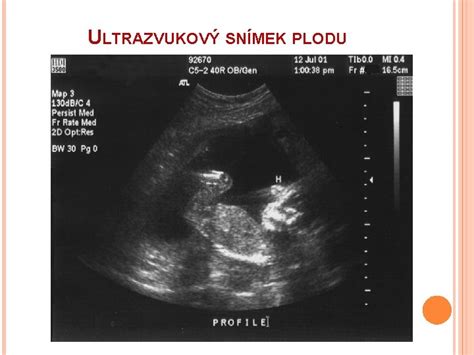

Ide o podrobné ultrazvukové vyšetrenie, ktorého podstatou je dôsledné preskúmanie bábätka, jeho chrbtice, orgánov a tvárových častí. Robí sa od 18. do 24. týždňa tehotenstva, no najideálnejším časom je 20. až 22. týždeň. Vtedy je bábätko dobre viditeľné, pretože ho obklopuje optimálne množstvo plodovej vody. Tento ultrazvuk je kľúčový aj preto, že v tomto období sa zvažuje ďalší postup v prípade, ak lekár nájde niečo, čo sa mu nepozdáva. Vtedy sa väčšinou pristupuje k ďalším vyšetreniam, ktoré by mali byť urobené čím skôr, pretože tehotenstvo je možné ukončiť zo zdravotných dôvodov do 24. týždňa.

Morfologický ultrazvuk je štandardné anatomické vyšetrenie plodu, ktoré odporúča Slovenská spoločnosť ultrazvukovej diagnostiky v prenatálnej medicíne (SSUM). Podľa týchto odporúčaní sa realizuje vo väčšine primárnych gynekologických ambulancií. Počas tehotenstva absolvuje žena množstvo vyšetrení, ktorých cieľom je monitorovanie zdravého vývoja plodu a včasné odhalenie prípadných abnormalít. Medzi kľúčové vyšetrenia patrí morfologický ultrazvuk, ktorý sa zameriava na detailné zobrazenie orgánov a systémov plodu.